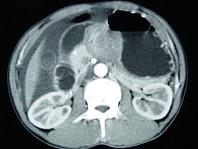

问题 男,65岁,中上腹痛腹胀、消瘦、乏力、纳差,影像检查如图,最可能的诊断是()

选项 A.胃间质瘤 B.萎缩性胃炎 C.肥厚性胃炎 D.胃窦癌 E.胃淋巴瘤

答案 D